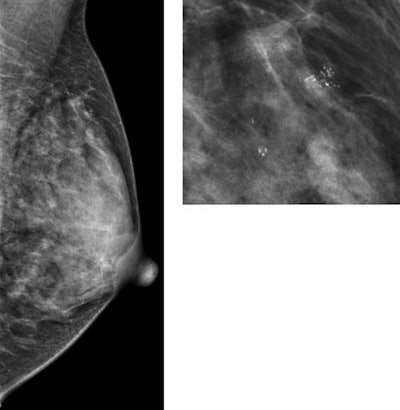

Not all benign findings on screening mammography are equal. A Spanish team identified two characteristics of benign lesions that signal an increased risk of future malignancy in new research presented on 3 October at the 2020 European Breast Cancer Conference.

Women with benign breast disease (BBD) found after their first mammogram or with breast tissue with a proliferative presentation had a much higher risk of developing breast cancer than their peers. The findings could one day be used to better personalize screening mammography, according to presenter Marta Román, PhD, an epidemiology researcher at Hospital del Mar Medical Research Institute in Barcelona, Spain.

The retrospective study included data from 629,087 women who collectively underwent more than 2.3 million mammograms between 1995 and 2015. The researchers followed the patients for an average of almost eight years in order to see whether an association existed between characteristics of benign breast disease and breast cancer occurrence.

Out of roughly 629,000 women, clinicians diagnosed 9,184 incidences of benign breast disease and 9,431 breast cancers. The researchers noted there was a strong association between any type of BBD diagnosis and breast cancer risk, but that risk varied based on screening type and whether or not the disease was proliferative.

After adjusting for age at diagnosis and screening year, women with benign breast disease diagnosed at their first mammogram had 1.87-times the risk of developing breast cancer than women without a BBD diagnosis. But that risk ratio increased to 2.67 for women with a BBD diagnosed after their first mammogram.

The results were similarly stratified depending on whether the findings were proliferative, a signal of increased growth of certain cell types. Women with proliferative BBD had 3.28-times the breast cancer risk of women without benign findings. In comparison, women with nonproliferative BBD had a risk ratio of 1.96.

These findings were compounded for women diagnosed with proliferative benign breast disease after their first screening mammogram. These women had almost four times the breast cancer risk of women without benign findings. Meanwhile, women diagnosed with nonproliferative BBD at their first mammogram had a much lower risk ratio of 1.63.